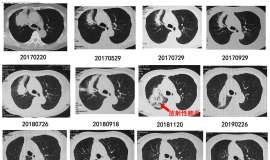

一年没有更新病情了,可能是治疗过程没有太大新意,还是一直进行靶向轮换和穿插化疗,唯一的区别就是放弃白紫了,改用温和一点的吉西他滨节拍化疗。去年端午节前后,出现下肢静脉血栓,进行取栓手术,其他一切安好 ...